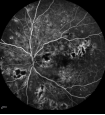

中期糖网血管闭塞及新(xīn)生血管形成

晚期糖网